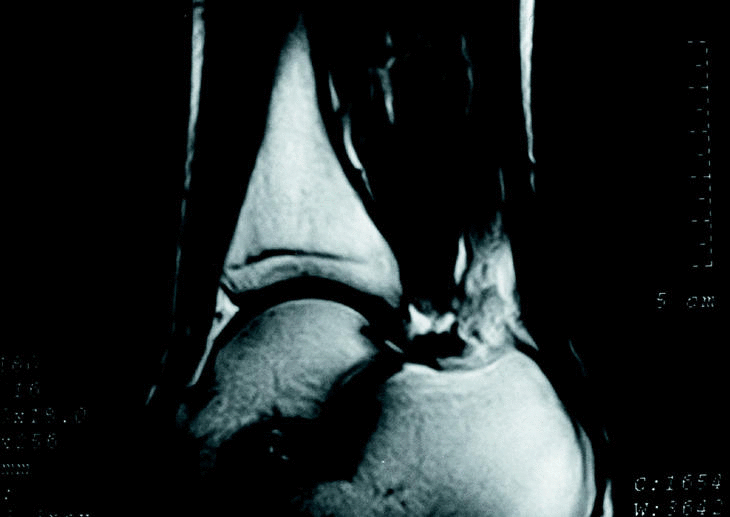

Desde 1990, se han identificado en el Servicio de Cirugía Ortopédica y Traumatología del Hospital USP-Santa Teresa de La Coruña 10 casos de músculos sóleos accesorios en 7 pacientes (tres casos bilaterales). Se trataba de 4 hombres y 3 mujeres, con una media de edad de 25 años (mínima: 4 y máxima: 42 años). En 6 casos, los pacientes acudieron a la consulta por presentar dolor en la zona aquílea durante el ejercicio físico, identificándose otros 2 casos al examinar el lado contralateral y un caso bilateral (el niño de 4 años) acudió a consulta porque sus padres estaban inquietos entre el aspecto de las regiones retromaleolares tibiales. En la exploración física se apreciaba en todos los casos, una tumoración retromaleolar interna del tobillo (fig. 1), ocasionalmente sensible a la palpación y que provocaba molestias con los ejercicios de estiramiento selectivo del sóleo en aquellos casos previamente sintomáticos; el tendón de Aquiles aparecía de grosor normal y sin nódulos en su interior en todos los casos. En los casos en que se realizó un estudio radiográfico, se podía apreciar una obliteración del triángulo de Käger (grasa preaquílea) por una masa de partes blandas (fig. 2). En todos los casos, se realizó un estudio ecográfico en el que se confirmó la existencia de una masa preaquílea, bien delimitada, con una ecogenicidad similar a la del músculo estriado, que finalizaba a una distancia variable del calcáneo dependiendo de su tamaño (fig. 3). En los 2 primeros casos, se realizó además un estudio de RM para confirmar el diagnóstico de músculo sóleo accesorio (fig. 4). Tras el diagnóstico, se instauró un régimen de estiramiento selectivo del sóleo y reducción del nivel de actividad física hasta la desaparición de la sintomatología, seguida de la reincorporación progresiva a la actividad previa por debajo del nivel de molestia, hasta la normalización de los pacientes. En todos los casos menos uno (el paciente de más edad) fue posible retomar la actividad física sin limitaciones; en éste último caso, el paciente se encuentra subjetivamente mejor, aunque persiste el dolor al correr más de 15 a 20 minutos, por lo que se encuentra a la espera de decidirse a realizar una fasciotomía del sóleo accesorio.

Figura 4. RM del tobillo de un paciente portador de un músculo sóleo accesorio, cuya inserción alcanza el borde superior del calcáneo por medio del vientre muscular.